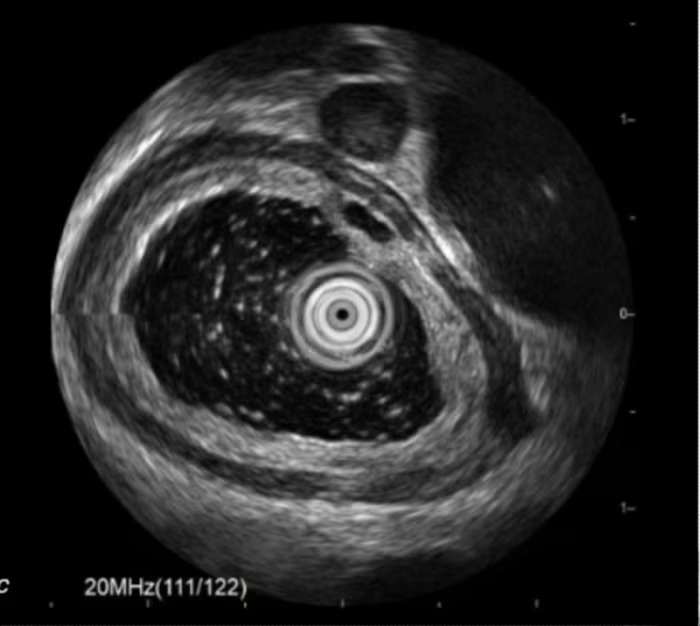

Nội soi siêu âm cho thấy khối u kích thước khoảng 0.5x0.2.0.7cm, giảm âm đồng nhất, ranh giới rõ, nằm ở lớp cơ niêm, không thấy chảy máu, vôi hóa trong u.

Hình ảnh u dưới niêm mạc xuất phát từ lớp cơ niêm, theo dõi u cơ trơn khi bệnh nhân A được nội soi siêu âm. Ảnh: BVCC

Trường hợp bệnh nhân A, trên nội soi siêu âm có khối u ở lớp cơ niêm của thực quản, giảm âm đồng nhất, giống tính chất lớp cơ. Đây là hình ảnh đặc trưng u cơ trơn, chưa có đặc điểm gì gợi ý ác tính (vôi hóa, chảy máu, loét bề mặt, nhú lồi trong u...).